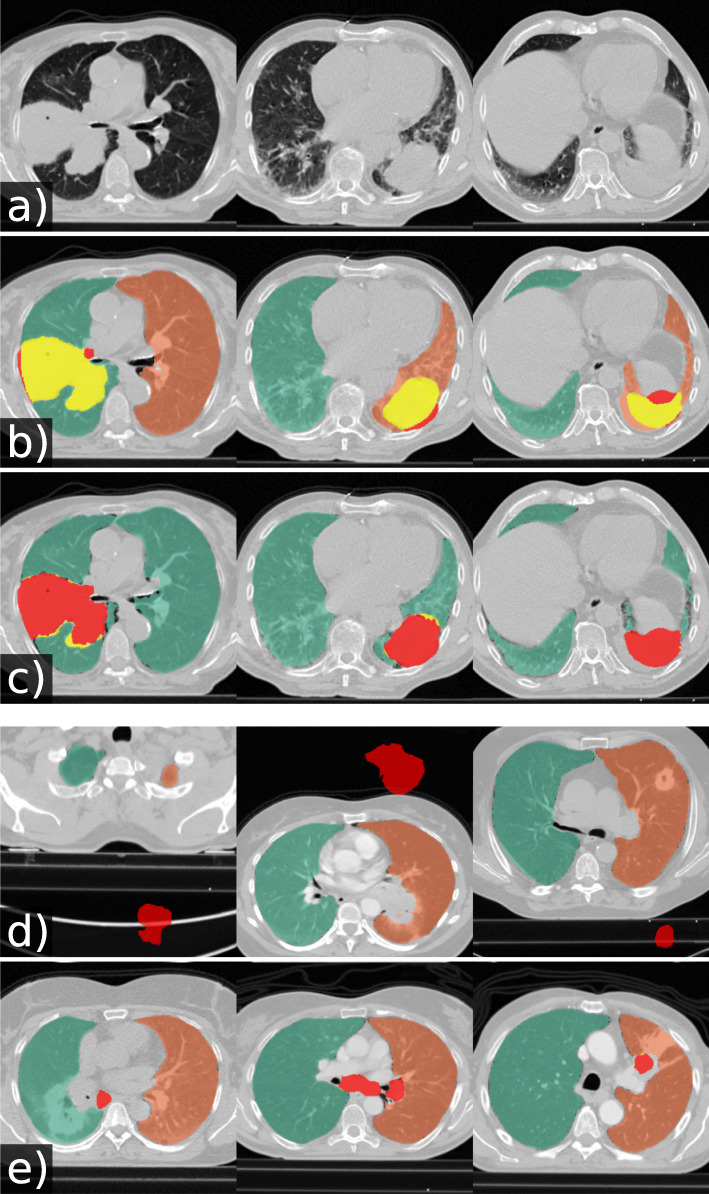

Table 5 and Fig. 4 show results for tumour overlap on the 318 volumes of the Lung1 dataset. U-net(R-231) covered more tumour volume mean/median compared to P-HNN (60%/69% versus 50%/44%, p < 0.001) and CIP (34%/13%). Qualitative results for tumour cases for U-net(R-231) and P-HNN are shown in Fig. 5b, c. We found that 23 cases of the Lung1 dataset had corrupted ground truth annotation of the tumours (Fig. 4d). Figure 5e shows cases with little or no tumour overlap achieved by U-net(R-231).

Fig. 4.

U-net trained on routine data covered more tumour area compared to reference methods. Box- and swarm plots showing the percentage of tumour volume covered by lung masks that were generated by different methods (318 cases)

Fig. 5.

Qualitative results of automatically generated lung masks for tumour cases. Yellow: tumour area covered by the lung mask. Red: tumour area not covered by the lung mask. Original images (a), lung masks generated by our U-net(R-231) (b), lung masks generated by P-HNN (c), corrupted tumour segmentations in the Lung1 dataset (d), and cases with poor tumour overlap of lung masks generated by U-net(R-231) (e)